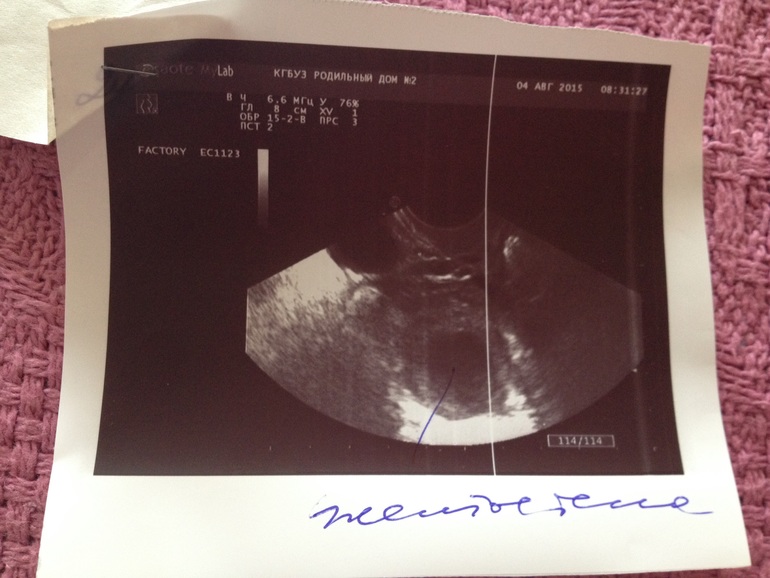

Узи на 24 дц.

Прошу помощи знающих, в расшифровке узи. Убежала из кабинета ничего не спросив, а к врачу только через несколько дней. Заранее благодарю)